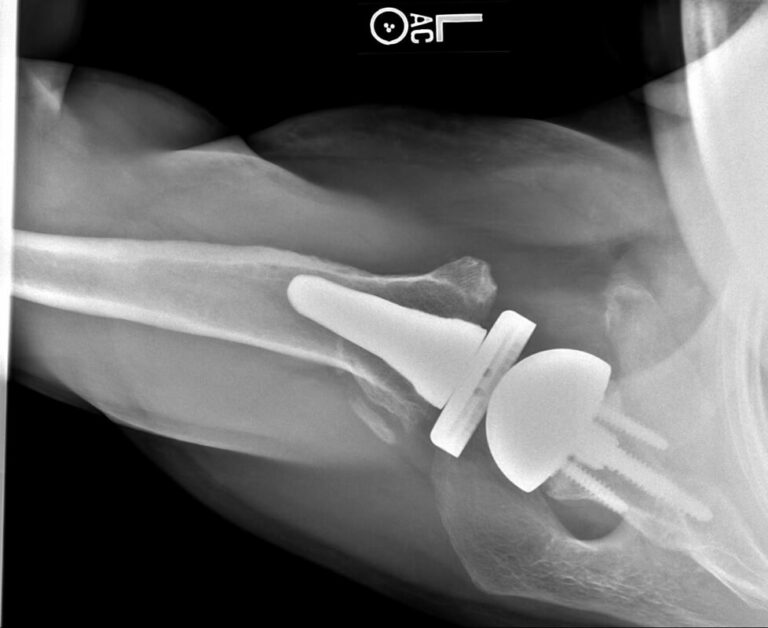

Stryker/Wright/Tornier, Ascend Flex